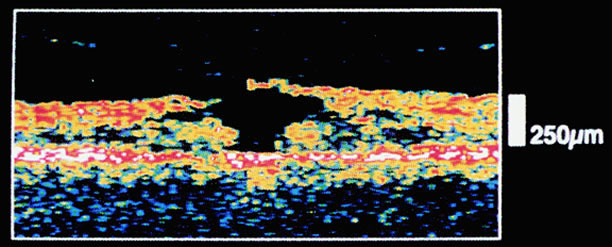

OCT confirms the complete detachment of the prefoveal vitreous cortex, intraretinal thickening resulting from cystic spaces, and elevation of the retina from the pigment epithelium surrounding the macular hole87,91 (Fig. 18).

Fig. 18. Stage 3 hole. Top. Optical coherence tomogram (3 mm long) shows the hyperreflective operculum (arrow) next to the minimally reflective membrane corresponding to the posterior hyaloid. The edges of the hole are thickened by cystic spaces and detached from the retinal pigment epithelium by 850 μm (arrowheads). Bottom. Composite optical coherence tomogram shows the detachment of the posterior hyaloid from the entire posterior hole. (OD, optic disc).